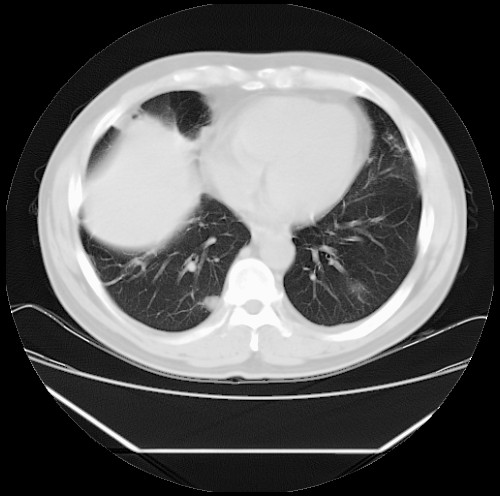

标题: CT22085:双肺多发结节

男,44岁,咳嗽,痰中带血2天。

病灶大部分位于胸膜下,结节大小相差不是很大,肺尖太干净。这种结核没见过,我认为可排除。

首先考虑转移,不除外肉芽肿、真菌感染。建议查其它。

除肺内及胸膜下可见多发大结节外,在肺小叶中心核、小叶间隔及支气管血管束上亦可见多方小结节,可以认为是随机分布。考虑转移可能性大。

仔细观察病灶形态,病灶边界部分清楚,结合临床症状,首先考虑转移,纵隔内多个肿大淋巴结影。

双肺血管纹理末端多发类圆形结节,边界光滑清晰 气管前腔静脉后淋巴结肿大

考虑转移瘤

沿血管分布,位于血管末端。转移瘤多见,血行性菌栓也可见到。

本例双肺多发类圆形高密度灶,边清,结合病史多考虑双肺多发转移改变,可以结合实验室检查。